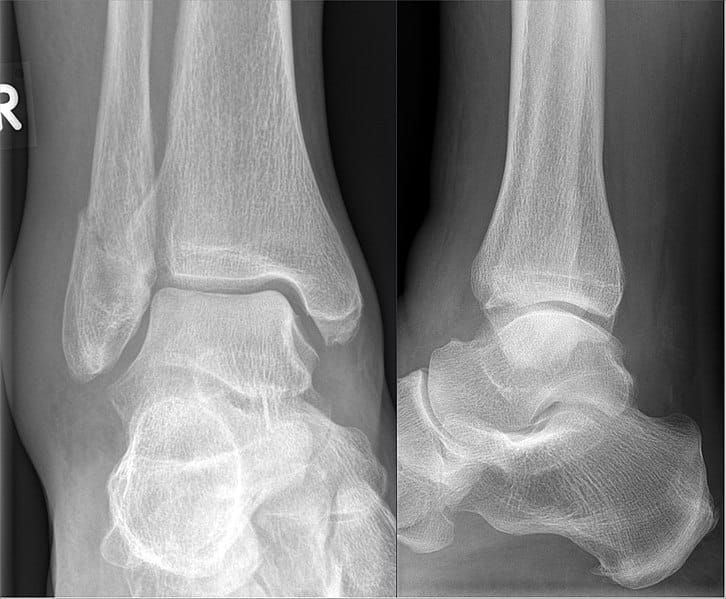

Bimalleolar Fracture X Ray . Bimalleolar fractures are a type of ankle fracture that involve both the lateral and medial malleoli at the distal ends of the fibula and tibia, respectively. Diagnosis is made with plain. Unstable weber b fracture of the right distal fibular and fracture of the medial malleolus (bimalleolar ankle fracture). Ankle fractures account for ~10% of fractures encountered in trauma, preceded only in incidence by proximal femoral fractures in the. These two bones articulate with the. A 'maisonneuve fracture' is a fracture of the proximal fibula associated with injury to the medial side of the ankle and disruption of the distal tibiofibular syndesmosis. Ankle fractures are very common injuries to the ankle which generally occur due to a twisting mechanism. The medial ankle injury may be either a visible medial malleolus fracture or an invisible injury of the medial ligaments.

Bimalleolar Fracture X Ray Ankle fractures account for ~10% of fractures encountered in trauma, preceded only in incidence by proximal femoral fractures in the. These two bones articulate with the. Ankle fractures account for ~10% of fractures encountered in trauma, preceded only in incidence by proximal femoral fractures in the. Diagnosis is made with plain. Bimalleolar fractures are a type of ankle fracture that involve both the lateral and medial malleoli at the distal ends of the fibula and tibia, respectively. The medial ankle injury may be either a visible medial malleolus fracture or an invisible injury of the medial ligaments. A 'maisonneuve fracture' is a fracture of the proximal fibula associated with injury to the medial side of the ankle and disruption of the distal tibiofibular syndesmosis. Ankle fractures are very common injuries to the ankle which generally occur due to a twisting mechanism. Unstable weber b fracture of the right distal fibular and fracture of the medial malleolus (bimalleolar ankle fracture).